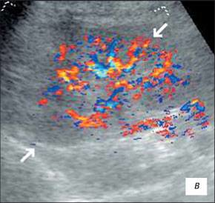

Доплерограма

На малюнку помітно зниження функції нирок виявляється ненасичений інтраренального малюнка, зниження по часу або мінімальної швидкості кровотоку. Всі ці критерії характеризуються патологією і потребують оперативного втручання.

На доплерограмі сечоводів СМР 2,3 і4 ступені спостерігається: делятація сечівника в нижніх і верхніх відділах при середньому або максимальному наповнені сечового міхура, циклічні зиіни діаметра сечівника в нижніх і верхніх відділах: доплерографічна регістрація зворотнього току сечі в сечоводі:стабільне розширення миски: зменшення розмірів нирки.